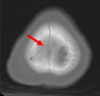

Acute blood shows up brighter on which type of scan. X-ray CT MRI T1 MRI T2 Ultrasound

**CT**

Which vessel is most likely to have ruptured? Left anterior cerebral artery Right anterior cerebral artery Left middle cerebral artery Right middle cerebral artery

The **right middle cerebral artery** is the most likely to have ruptured in this scenario, as this travels out laterally to supply the lateral region of the cortex.